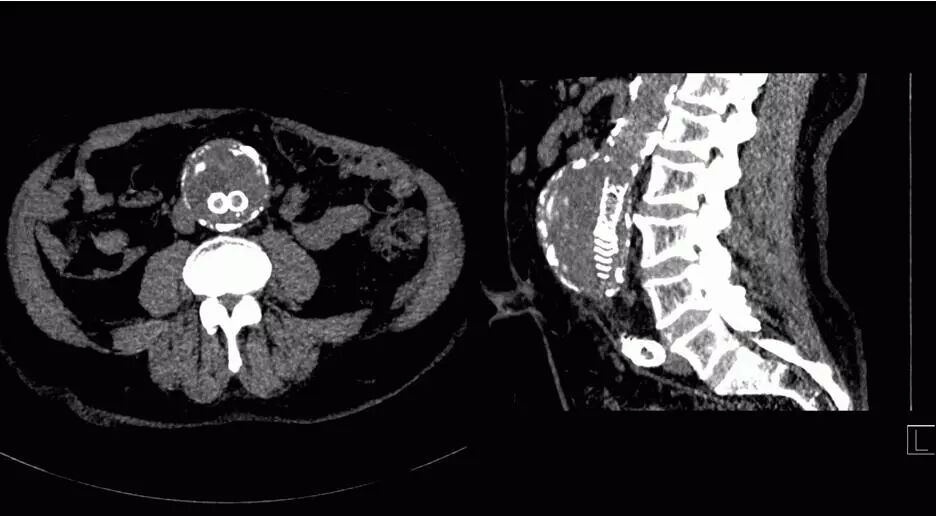

SOMATOM Force 突破技術(shù)界限,將血流評估覆蓋范圍擴大至80cm,特別適合大范圍下肢血管疾病診斷,一次掃描一次注射即可無創(chuàng)精確判斷病變,更加精確地制定臨床決策,選擇合理的治療方法。

△80厘米無創(chuàng)CT DSA,影像決策診療